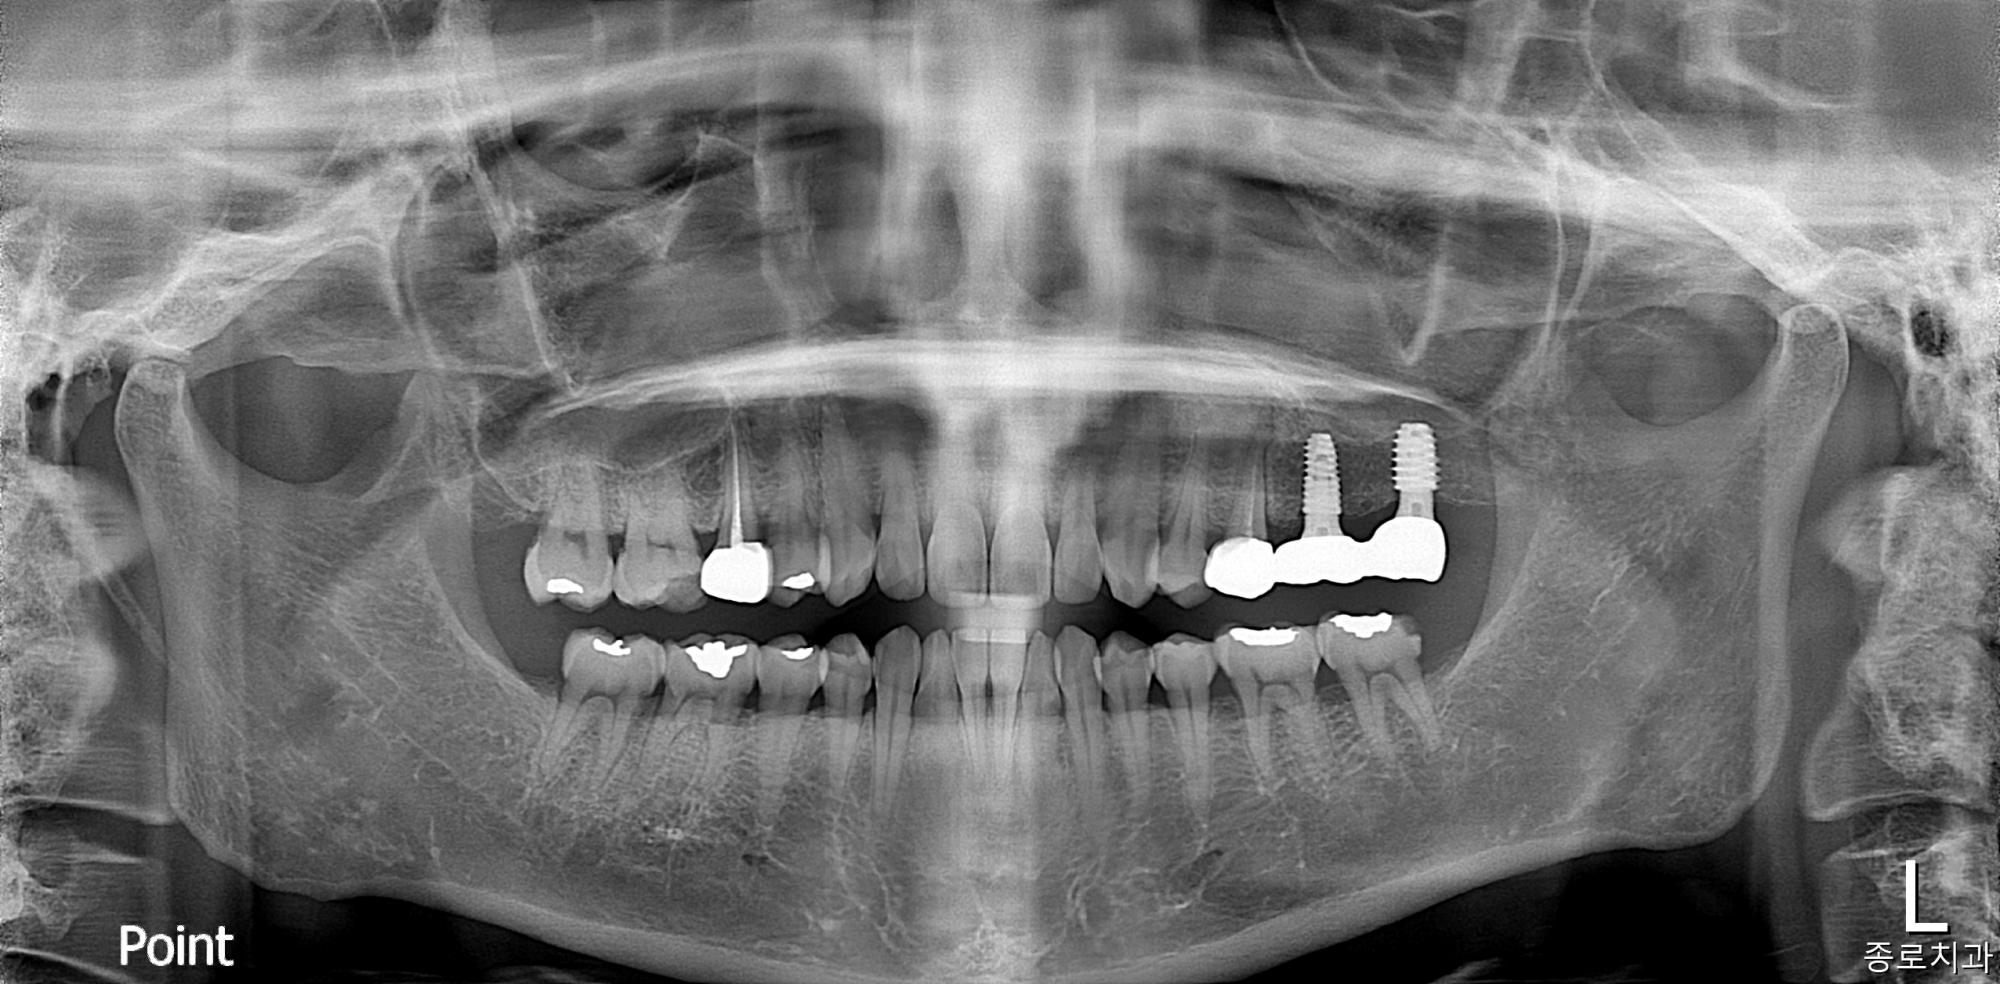

전/후 사진

임플란트